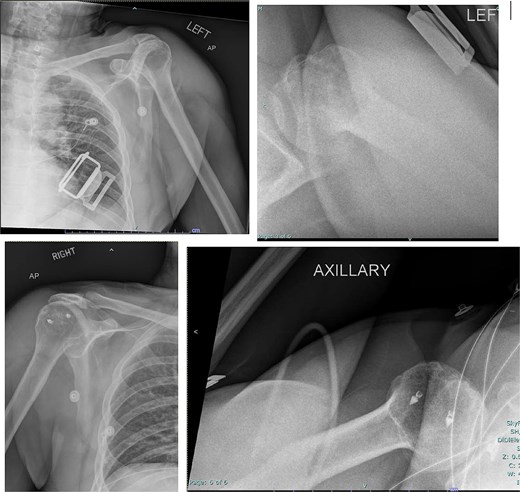

Both shoulders were reduced urgently by the orthopedic team, with immediate improvement in paresthesias (Fig. 2). Post-reduction CTs were significant for bilateral chronic rotator cuff disease with superior migration of the humeral heads, right-sided supraspinatus and subscapularis atrophy, and a left nondisplaced glenoid fracture (Figs 3 and 4). He was discharged home in bilateral slings.

Post-reduction X-rays demonstrating congruency restored to right and left glenohumeral joints, with evidence of superior humeral head migration bilaterally.

Post-reduction CT of the left shoulder demonstrating superior humeral head migration relative to the glenoid.

Post-reduction CT of the right shoulder demonstrating superior humeral head migration relative to the glenoid, visualized evidence of prior rotator cuff repair surgery, and a nondisplaced anterior-inferior glenoid fracture.